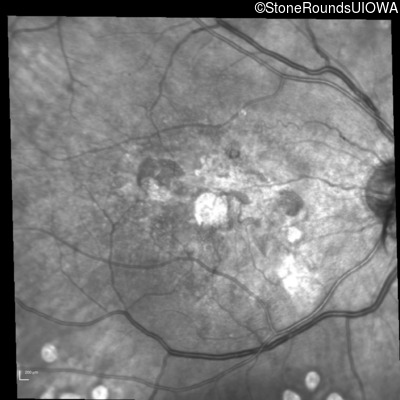

Infrared Fundus Photograph - Right - 20/150

Exemplar